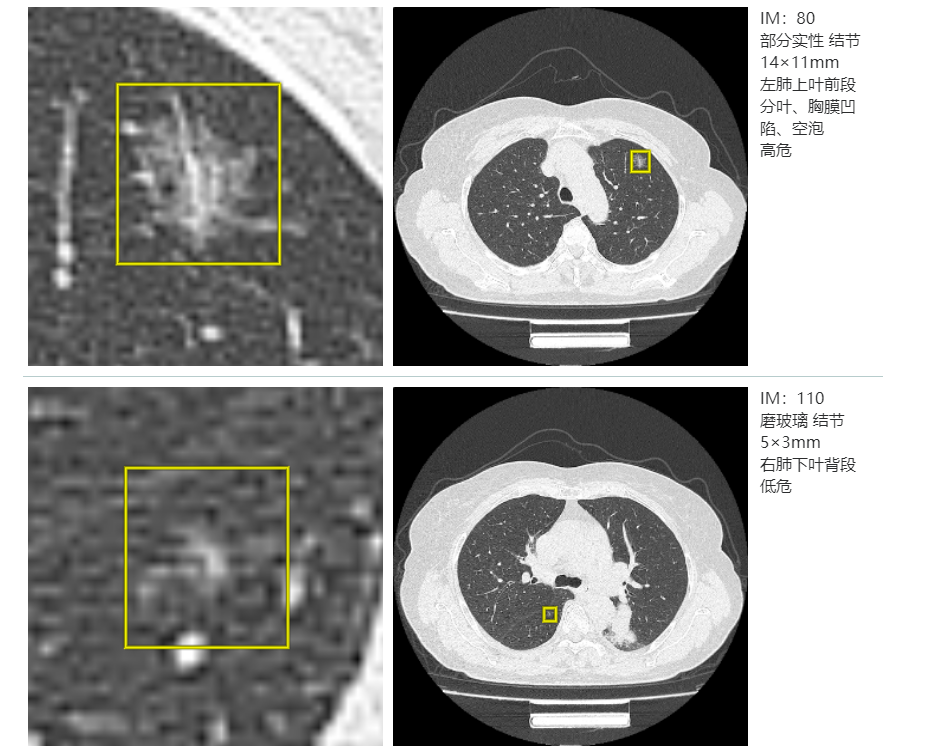

精准筛查是肺结节诊疗的第一步。汶上县人民医院在CT筛查领域率先实现“双智能化”升级,引入两套顶尖AI辅助系统——深睿医疗及联影智能模块,均实现长期正式部署与HIS系统深度融合,打造县域少有的“双AI协同”筛查模式。为群众提供更精准、更可靠的筛查服务,开启肺结节精准筛查“双保险”时代。

两套AI一起干活有什么好处?

算法不同,侧重点不同,相当于两个顶尖专家一起看片,互相核对;1毫米的小结节、淡淡的磨玻璃影,人眼容易漏,AI一抓一个准;能精准量出结节的尺寸、密度,还能对比对历史影像、量化结节变化,为长期随访和诊疗决策提供核心依据。

“两套AI互相印证,遇到疑难影像也会主动‘报警’,医生再启动人工复核,最大程度避免漏诊误诊。”心胸外科闫春章主任介绍道。